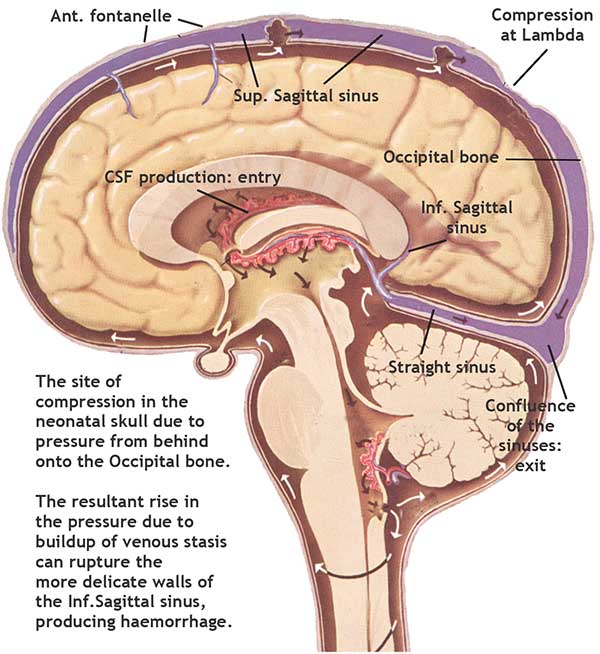

‘Structural Cranial’ techniques for relieving intracranial pressure and impacted

1986: As a result of five years of research into the hydrodynamics of intracranial physiology, I had an article published in the Journal of Alternative Medicine This was based on research into breathing patterns and their effects on intracranial pressure patterns.

1993-1995: Another article: Cranial osteopathy and the Pediatric Craniopathies was published by Bastyr University, Journal of Naturopathic Medicine ( Oregon ), and The New Zealand Journal of Osteopathy and by Temple University ( Philadelphia), Frontier Perspectives.

1989-1995: I gave seminars in New York, Philadelphia and Connecticut on 'An Osteopathic approach to intracranial physiology'. I was asked to join a clinic in Philadelphia and Danbury, Connecticut as an ‘expert’ diagnostician. These were short stints, I could not leave my London practice for too long.

Article published in three different journals globally on Infantile Craniopathies and Sudden Infant Death Syndrome.

I also developed the concept of a 'Pineal diaphragm'. This acts as valve and sensor which has an influence of the balance of CSF pressures between the central and peripheral CSF circulatory divisions.

'Give your body a gift for life.' The physiological basis for Enhanced Cranial technique.

The physiological basis for Enhanced Cranial technique.

The brain pulsates as we breath and with our heartbeat (watch the movie of this amazing new discovery). This makes the cerebro-spinal fluid flow and mix throughout our central nervous system. Thus when we increase our heart rate it 'clears' our head.  Research on the beneficial effects of massage.